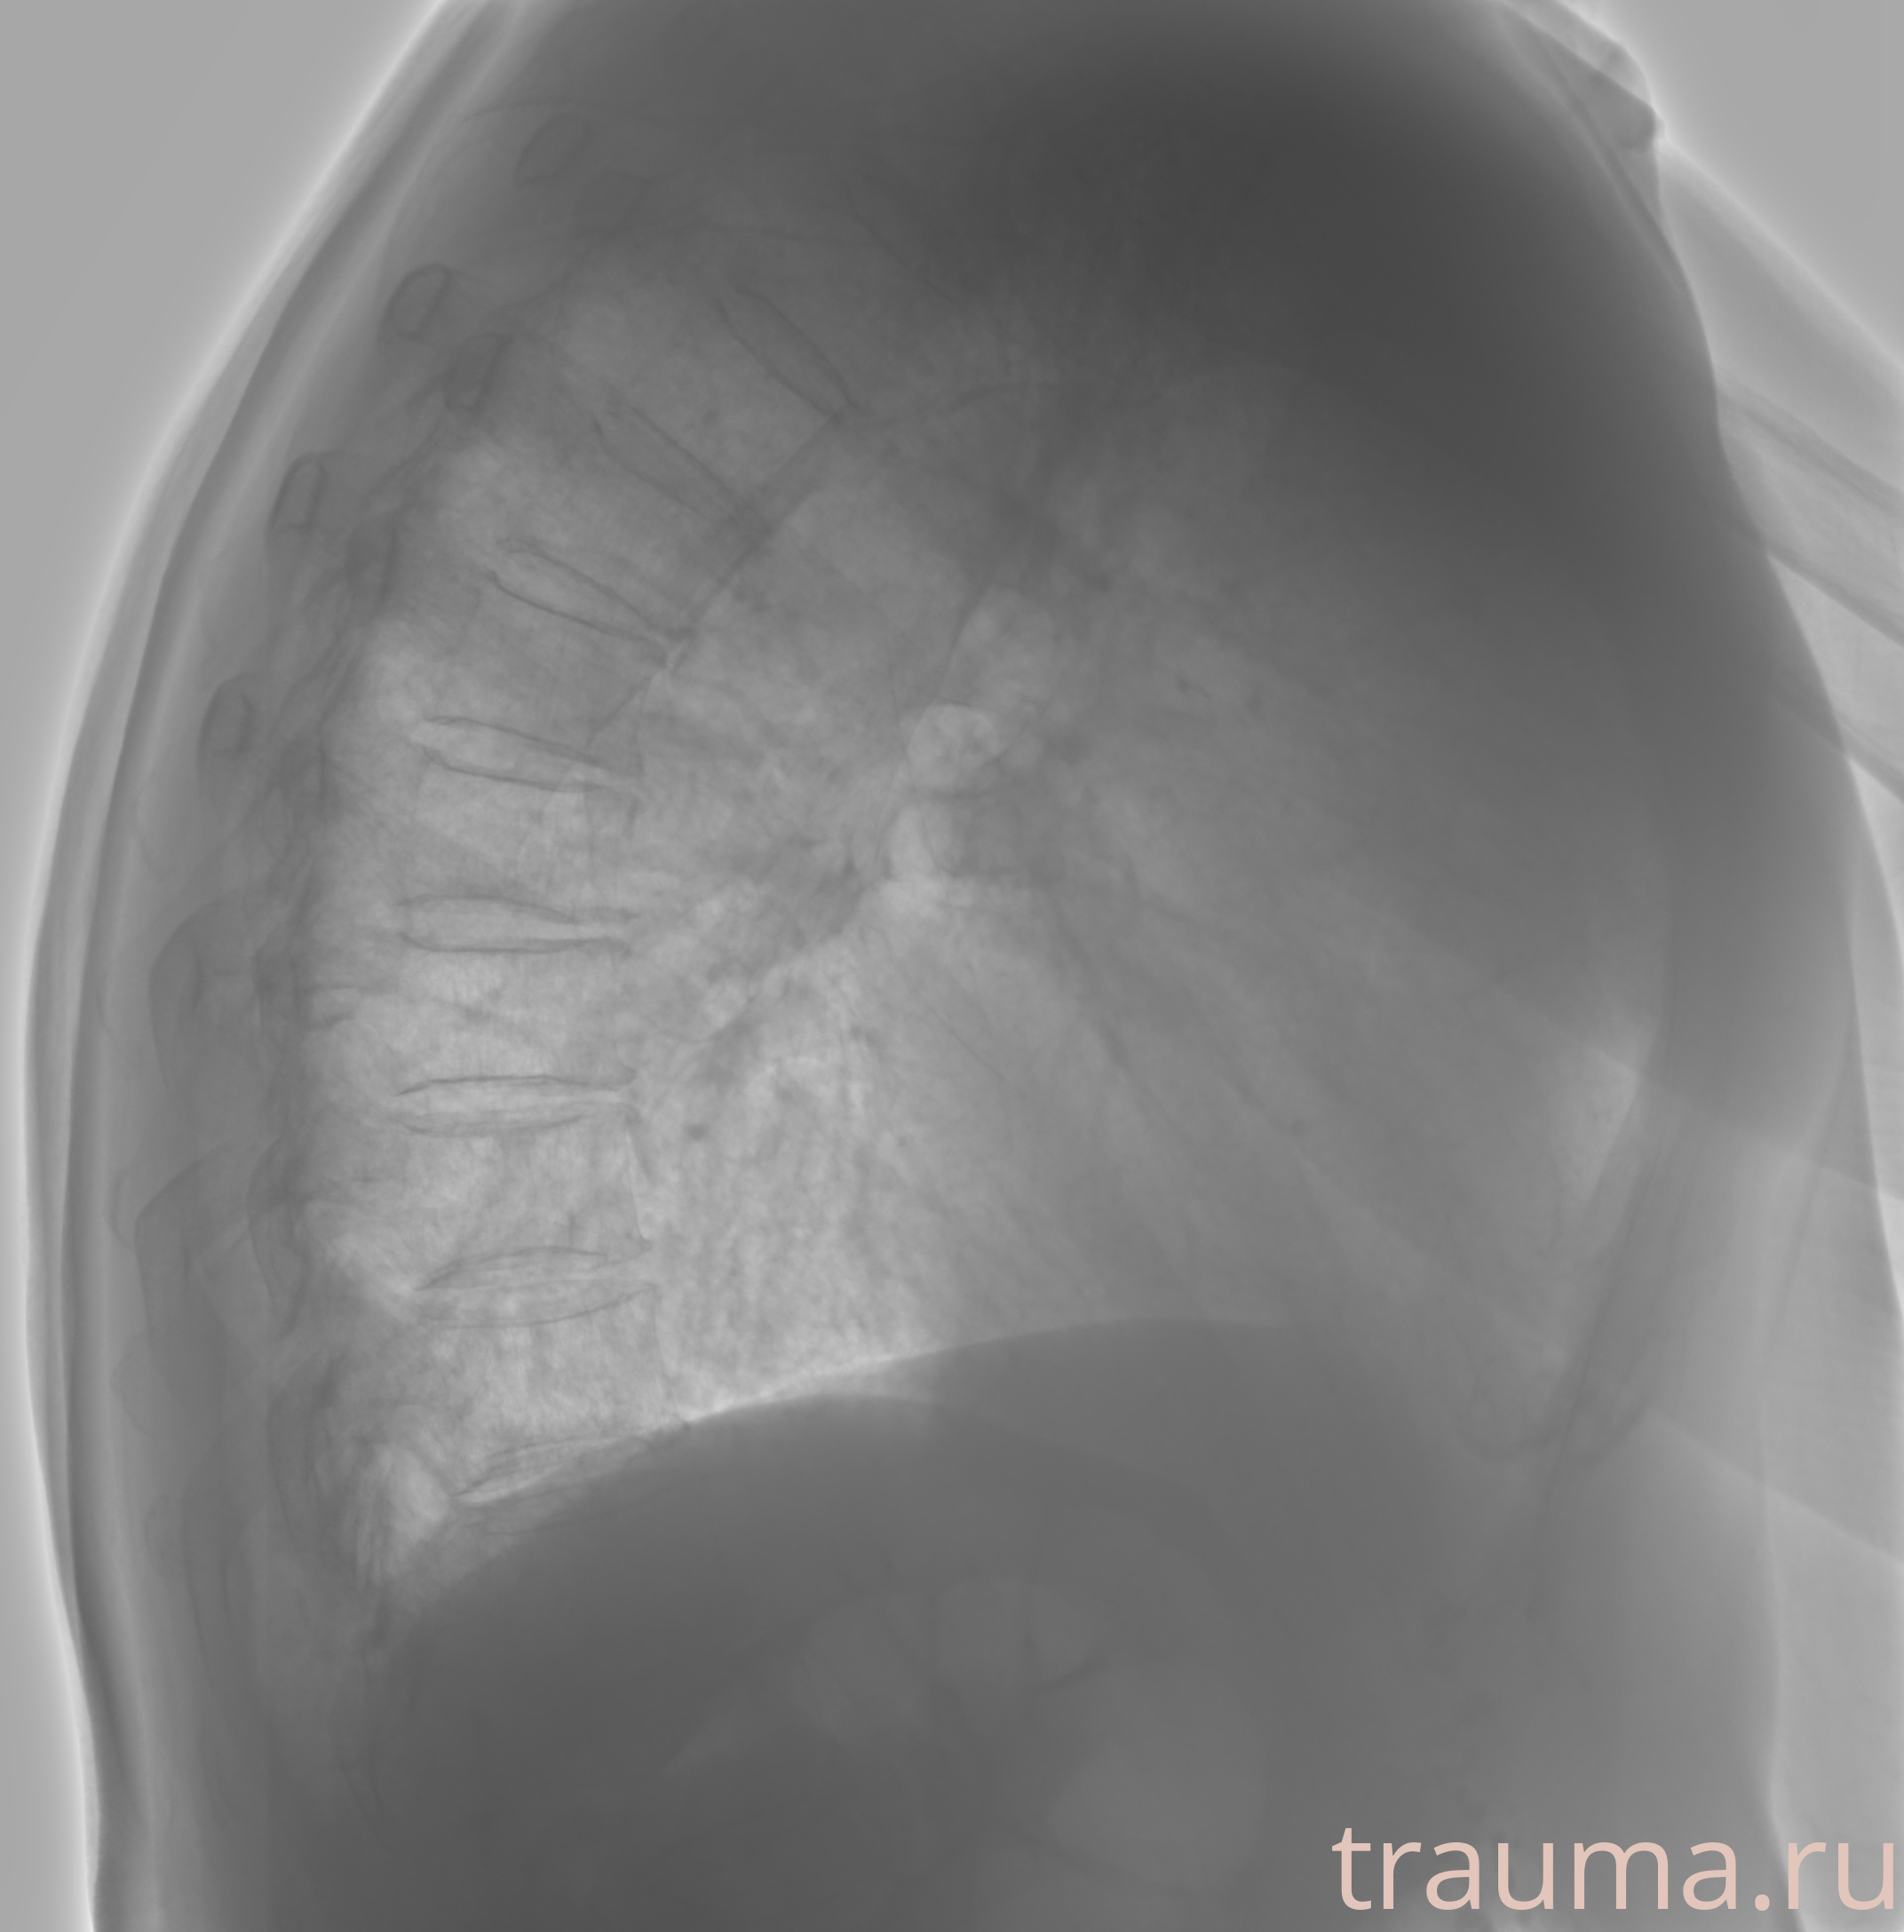

Рентген на дому: по вашему адресу приезжает врач-рентгенолог, травматолог-ортопед с мобильным рентгеновским аппаратом, проводит диагностику травмы или заболевания, делает необходимые рентгенограммы, дает рекомендации по дальнейшему лечению. Получить качественные снимки в домашних условиях возможно благодаря уникальной методике, разработанной МосРентген Центром для института  Склифосовского